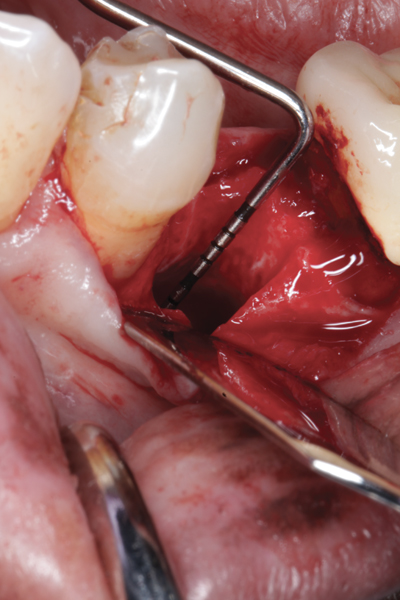

The four presented cases shown in Figure 1 through Figure 25 were all treated in a similar manner as outlined in detail in the captions for the first case (Figure 1 through Figure 11). In all four cases, teeth with pathosis were removed, buccal and lingual flaps were elevated, and sites were surgically debrided. A Cytoplast d-PTFE barrier was sized and inserted usually under the buccal flap, the bone graft was added, the barrier was then tucked under the lingual flap, and the flaps were sutured. Bone grafts were used in all of the cases, because buccal bony plates were resorbed and the bone graft helped support the barrier.

Fig 2. Buccal flap elevated exposing buccal plate defect.

Figure 2